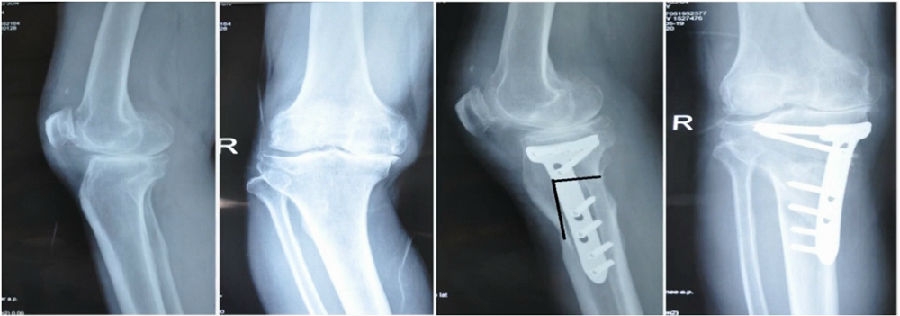

典型病例,男性,65岁,农民,双膝内翻16度。

术前影像

第一次为该患者做了传统上行开放截骨,撑开角度较大,术后用三种方法测量髌骨高度,发现髌骨高度受到影响,髌骨变低了。

左膝上行OWHTO(初次)

上行OWHTO髌骨高度测量

ISI法测量髌骨无明显变化;CDIBPI法测量髌骨降低明显;患者屈膝锻炼困难。

第二次来院做另一侧肢体时,采用下行截骨,术后患者髌骨高度,无论用哪种方法测量都无明显变化,而且患者膝关节功能迅速得到恢复。

右膝下行OWHTO(再次)

下行OWHTO髌骨高度测量

ISI法测量髌骨无明显变化;CDIBPI法测量髌骨无明显变化;患者屈膝明显改善。